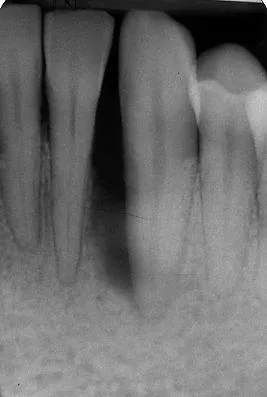

Des biomatériaux de synthèse seront utilisés afin de regagner, quand cela est possible, l’os partiellement détruit par la parodontite.

Des techniques chirurgicales de préservation papillaire permettent de régénérer les tissus parodontaux en garantissant leur maintien esthétique. Ces techniques chirurgicales avancées s’effectuent sous aides optiques grossissantes et avec des instruments micro chirurgicaux spécifiques.

Avant l’intervention

Quelques semaines après l’intervention